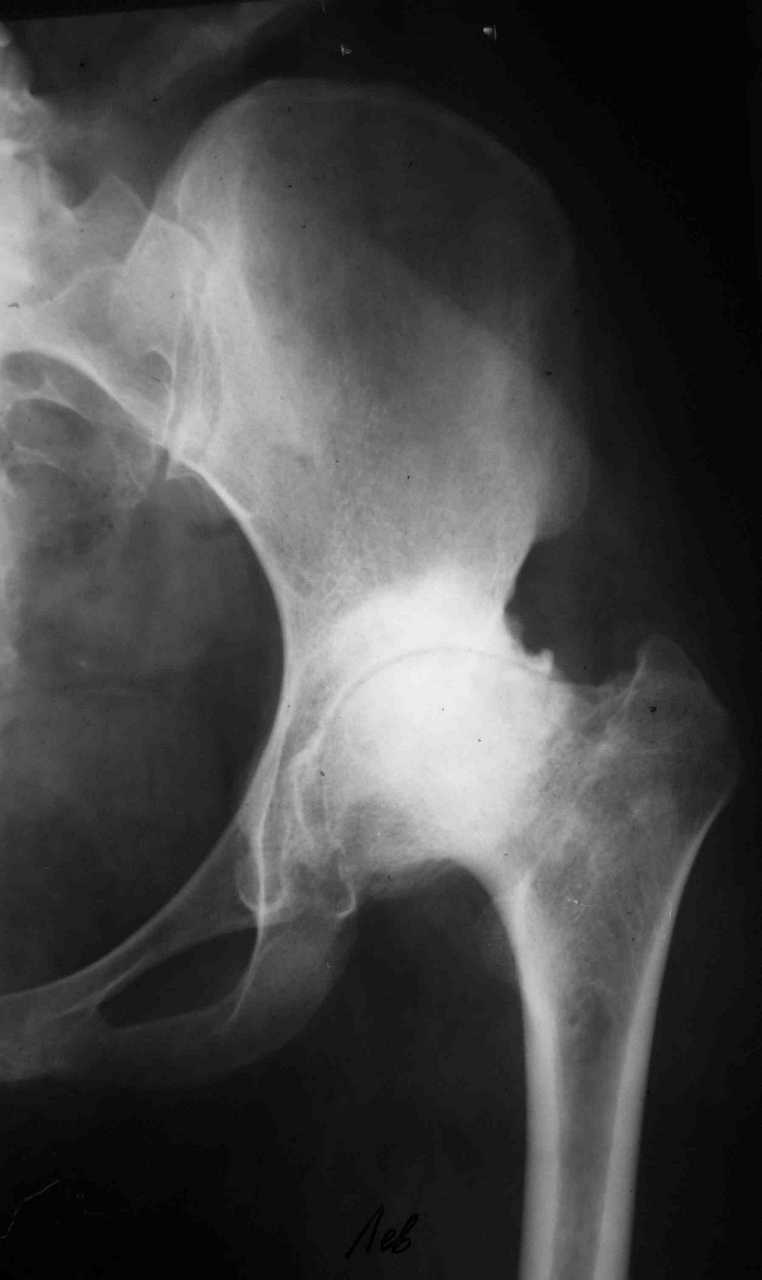

Уважаемые коллеги! К мне обратилась моя бывшая пациентка, 22 лет, с просьбой об эндопротезировнии коленного сустава. От артродеза категорически отказывается.DS: Врождённая аномалия развития левой нижней конечности. Состояние после удлинения бедра и голени (около 45 см). Варусная деформация шейки лев. бедра. Лев. коксартроз II ст. Лев. гонартроз III ст. Разгибательная контрактура лев. коленного сустава. Парез малоберцового нерва слева. Укорочение лев. н/конечности 1,5 см. Жалобы: на боли и нарушение функции в лев. коленном суставе.St. localis: ходит в брейсе с опорой на 1 трость. Относительная длина ног S – 1,5 см. Движения в лев. т/б суставе: сгиб. 70, разг. 180, привед. 60, отвед. 110, вн. рот. 20, нар. рот. 10; в лев. к/сус. пассивно: сгибание 0, разг. - 180+ 30; активно на переразгибание и из положения переразгибание на сгибание 2балла. Под нагрузкой вальгусно-рекурвационная деформация: клиничски на val. – 15-20, rec. - 30. Движения в лев. голеностопном суставе (акт./пас.): тыл. фл. 0/90, под. фл. 170, отвед. 10/15, прив. 25. Функция в других суставах не нарушена.Предполагаю, что наиболее лучшим вариантом будет двух этапное протезирование. На первом этапе – устранить антекурвацию на бедре аппаратом Илизарова; вторым этапом – протезирование – заднее-стабилизирующим протезом фирмы «Zimmer», т.к. маленькие размеры бедренной и большеберцовой костей.Возможны ли другие варианты лечения? Возможно ли одно этапное протезирование?Целесообразно ли в данном случае протезирование? Может быть не стоит идти «на поводу» у пациентки.Буду очень признателен всем, кто откликнется на мою просьбу.С уважением Игорь Атманский.

Уважаемый Игорь Александрович! Для принятия решения в данной непростой клинической ситуации необходимы снимок таза, и осевые снимки всей нижней конечности с захватом тазобедренного и голеностопного суставов. Похоже, там не только одна антекурвационная деформация бедра. Сохранились ли связки и в каком состоянии находятся мышцы после удлинения 45 см на фоне врожденной аномалии? Если на сегодняшний день конечность опорная, а опора безболезненная, то надо ли экспериментировать с эндопротезированием? В 22 года пациентке надо еще много успеть сделать: родить детей, получить специальность и т.д.

В настоящее время нет возможности сделать осевые снимки всей конечности. Это всё чем я раполагаю на сегодняшний день.

Спасибо. Картина несколько прояснилась. А планов в отношении тазобедренного сустава нет? Или пациентку беспокоит только колено.